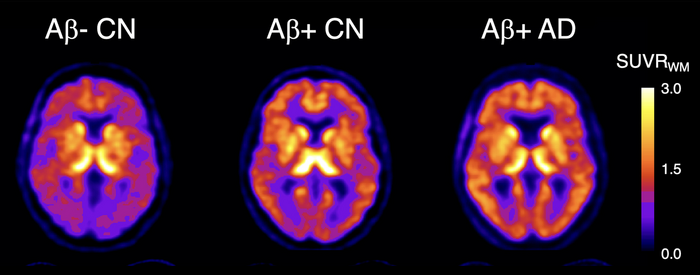

18F-SMBT-1 PET studies showed that beta-amyloid+ Alzheimer’s disease (AD) patients, but most importantly, beta-amyloid+ controls (CN) have significantly higher regional 18F-SMBT-1 binding than beta-amyloid- CN, with 18F-SMBT-1 retention highly associated with beta-amyloid burden. These findings suggest that increased 18F-SMBT-1 binding is detectable at the preclinical stages of beta-amyloid accumulation. Image created by Victor Villemagne, MD, Professor of Psychiatry at the University of Pittsburgh.

The three clinical groups were then classified based on their Aβ status (either as Aβ+ or Aβ-). No significant differences in 18F-SMBT-1 binding were found among Aβ- participants in the control and MCI groups. In the Aβ+ subjects with Alzheimer’s disease, 18F-SMBT-1 binding was significantly higher. Most importantly, 18F-SMBT-1 binding was significantly higher in the Aβ+ control group as compared to Aβ- control group.

“It’s of note that the brain regions where we saw this higher 18F-SMBT-1 binding in the control group are regions known for early Aβ deposition. This suggests that reactive astrocytes are associated with early Aβ deposition at the preclinical stages of Alzheimer’s disease and likely play a role over clinical progression,” said Villemagne.